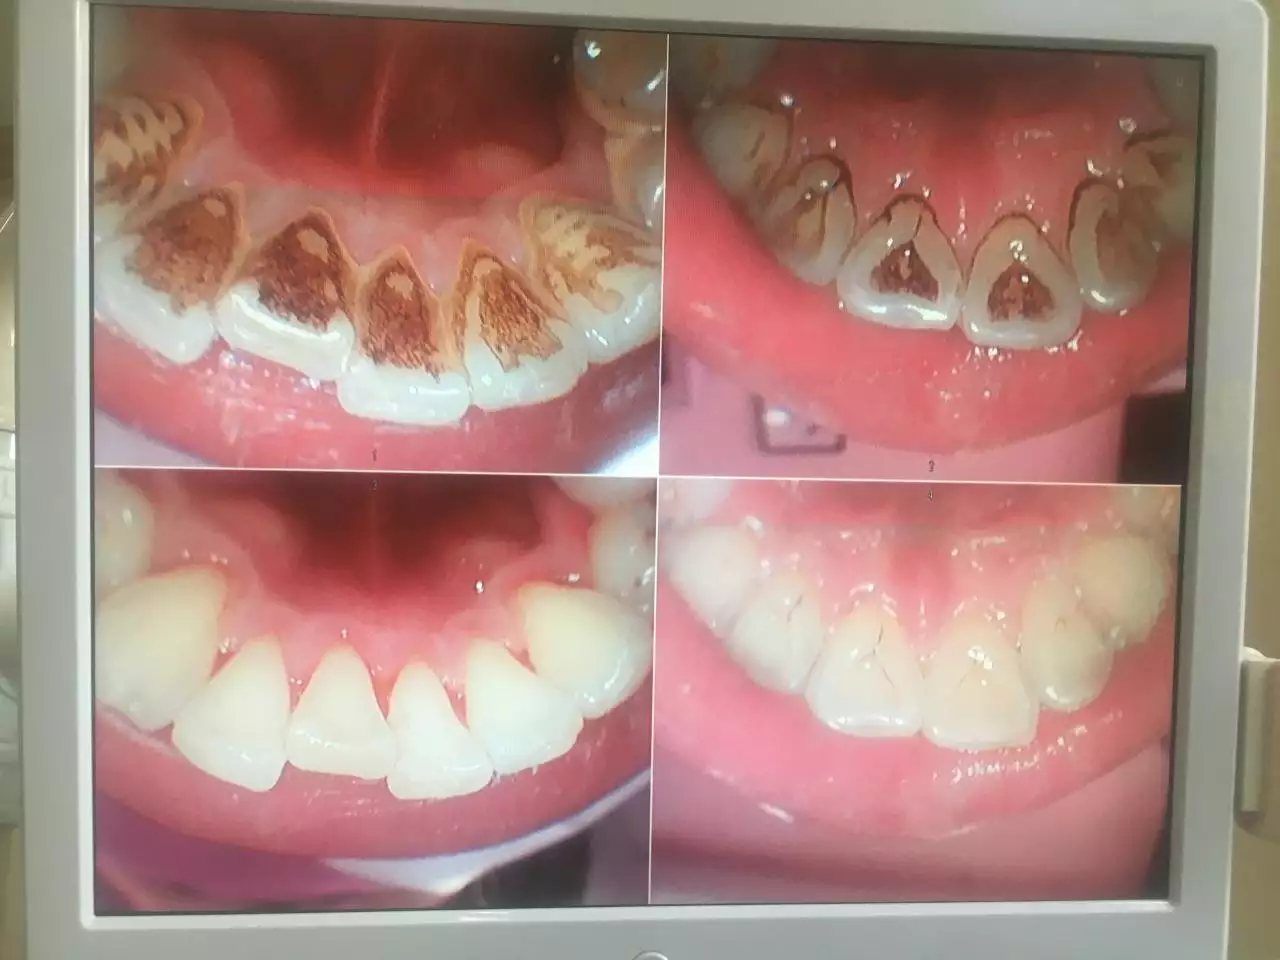

牙结石是很的东西,不去医院洗牙剔除不干净,要去医进行检查,拍片,然后才能确定**的方案。牙结石就是时间长了,细菌堆积而成,最开始牙结石是软的,时间长了就了,自己一个人是无法去除牙结石的,而且也去除不干净。老年人千万不要洗牙。

牙齿出现了问题,口腔出现了问题,一定要及时的去医院进行检查,每隔一段时间就要洗牙,牙齿残留的食物残渣,还有其他的细菌会很多,其实你好好刷牙也会有影响。比如我们每天喝的水,对牙齿也是有影响,如果我们吃的东西过咸,吃了很多甜的东西,对牙齿都有影响。当发现有牙结石这种情况的时候,**的方法就是进行洗牙。现在很多口腔医院,口腔诊所技术都很好,作为普通市民的我们,应该每隔一段时间就去做一下口腔检查,检查一下牙齿,看看有没有其他的疾病,有牙结石这种情况就要赶紧洗牙,避免引起其他的疾病。